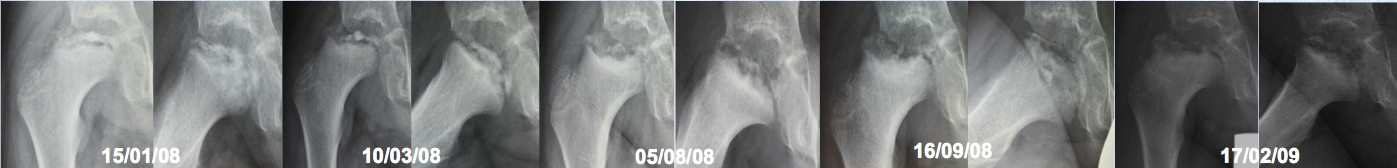

Enfermedad de Legg-Perthes-Calvé recurrente. Descripción de un caso y revisión de la literatura. [Recurrent Legg-Perthes-Calvé disease. A case report and literature review]